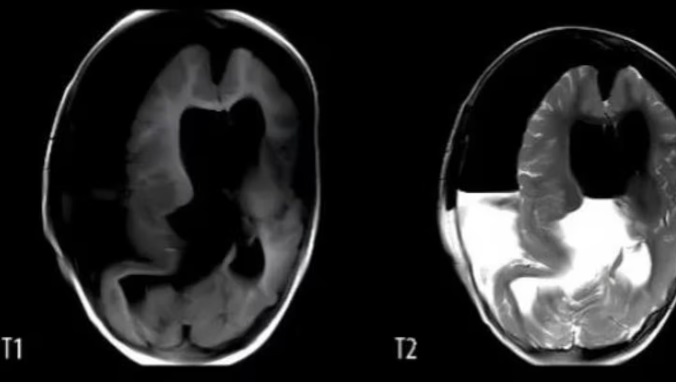

Según informa TN, una nena de un año tuvo que ser hospitalizada debido al gran tamaño de su cráneo y a que presentaba retrasos en sus habilidades motoras. Una vez internada le realizaron una tomografía que reveló que tenía un “tejido blando, hueso similar al de las extremidades y sombras de tejido óseo mixto en el área intracraneal”. Le realizaron una craneotomía y descubrieron que tenía un feto creciendo en su cabeza.

En el caso de esta pequeña, los médicos detectaron anomalías en su cráneo a las 33 semanas de gestación, durante un examen prenatal. Pero, la resonancia magnética no pudo proporcionar más información. La beba nació por cesárea a la semana 37 y los médicos notaron que su cabeza era notablemente más grande que lo normal.

Tras de la craneotomía que le realizaron, los médicos explicaron: “Extrajimos un embrión inmaduro, con vérnix y órganos visibles, como la boca, los ojos, la cabeza fetal, el pelo fetal, el cuerpo, el antebrazo, las manos y los pies”. A su vez, informaron que el embrión medía 18 cm de largo, tenía rasgos y extremidades malformadas, así como huesos largos y una columna vertebral.